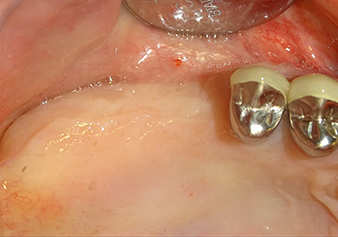

Implantation and prosthetic restoration

To move the augmentation material in the direction of the maxillary sinus atraumatically, the implant was inserted very slowly by hand (Fig. 9). In the process, the membrane was pushed in the cranial direction once again. After two months, the surgical site healed without irritation. Six months later, the x-ray check showed a significant increase in opacity as an indication of ossification (Fig. 10). The prosthetic restoration was carried out with a metal-ceramic crown.

In the author’s practice, the membrane is routinely lifted in two phases. Alternatively, the method specified by the manufacturer is also suitable. In this case, the implant bed is first prepared and only then is the bony sinus floor opened on a small scale with the Z35P instrument. As a result of the very atraumatic method, the patient experienced no postoperative pain and was able to return to work the following day. In the author’s practice, this is true of 90% of patients.